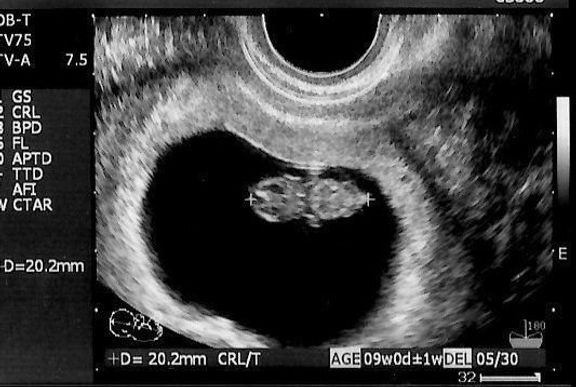

"おなかの中はどうなっていくの? エコー写真で振り返る、高齢ママのはじめての妊娠生活" -

待望の妊娠判明!エコー写真に見る、我が子を胸に抱くまでの“命の軌跡275日” -